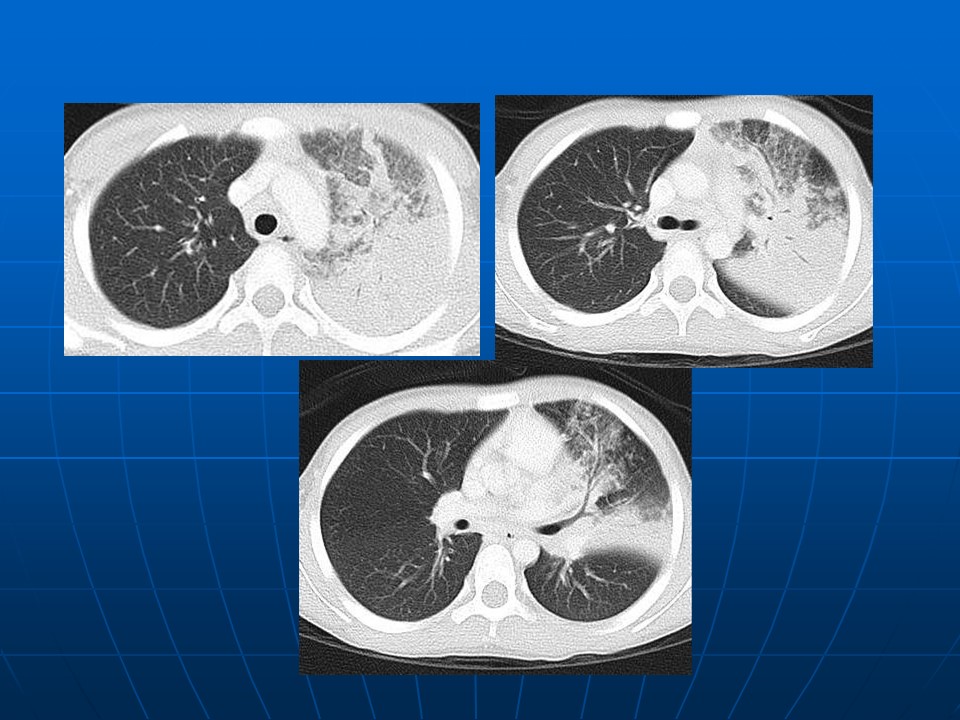

【PPT】早期肺癌易漏诊征象分析